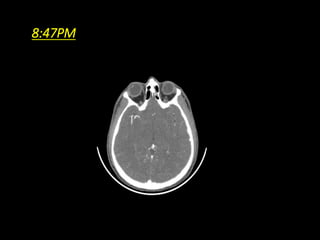

8:47PM

PATIENT - 8JULY • 35/M C/O SUDDEN ONSET WEAKNESS OF LEFT UPPER AND LOWER LIMB • TIME – SINCE 6 PM ON 8 JULY

DSA PATIENT SHIFTED INAT 10:30PM PUNCTURE – 10:35PM